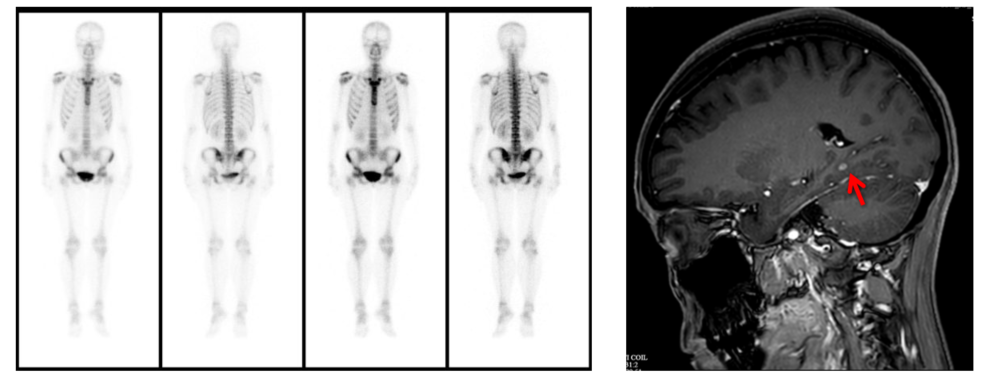

• 全身骨显像(2025-4-19): 未见明显异常。

12.png

全身骨显像及颅脑增强MRI

• 颅脑增强MRI(2025-4-18): 右侧颞枕部单发转移瘤,长径约3mm。